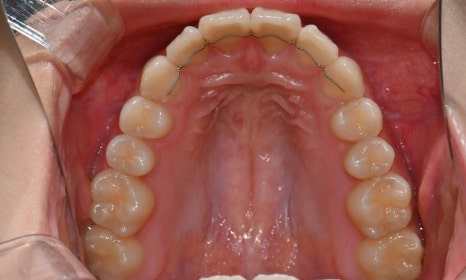

2025.3. 초진 (앞니 경미한 총생과 과개교합) - 연세정원치과

정밀진단 결과 위아래 앞니가 약간 겹쳐 있어 배열이 고르지 않은 상태였으며, 약간의 과개교합이 동반된 상태였습니다. 다만 골격적인 문제나 안모 불균형은 없었고, 측면에서도 돌출감 없이 비교적 안정적인 안모를 유지하고 있었습니다.

이번 케이스는 인비절라인 Comprehensive로 치료를 진행하였으며, 치아 이동은 과도하지 않게 단계적으로 진행하기 위해 치간삭제를 최소한으로 적용하며 공간을 확보하는 방향으로, 총 33단계의 장치를 통해 치아 이동을 계획하였습니다.